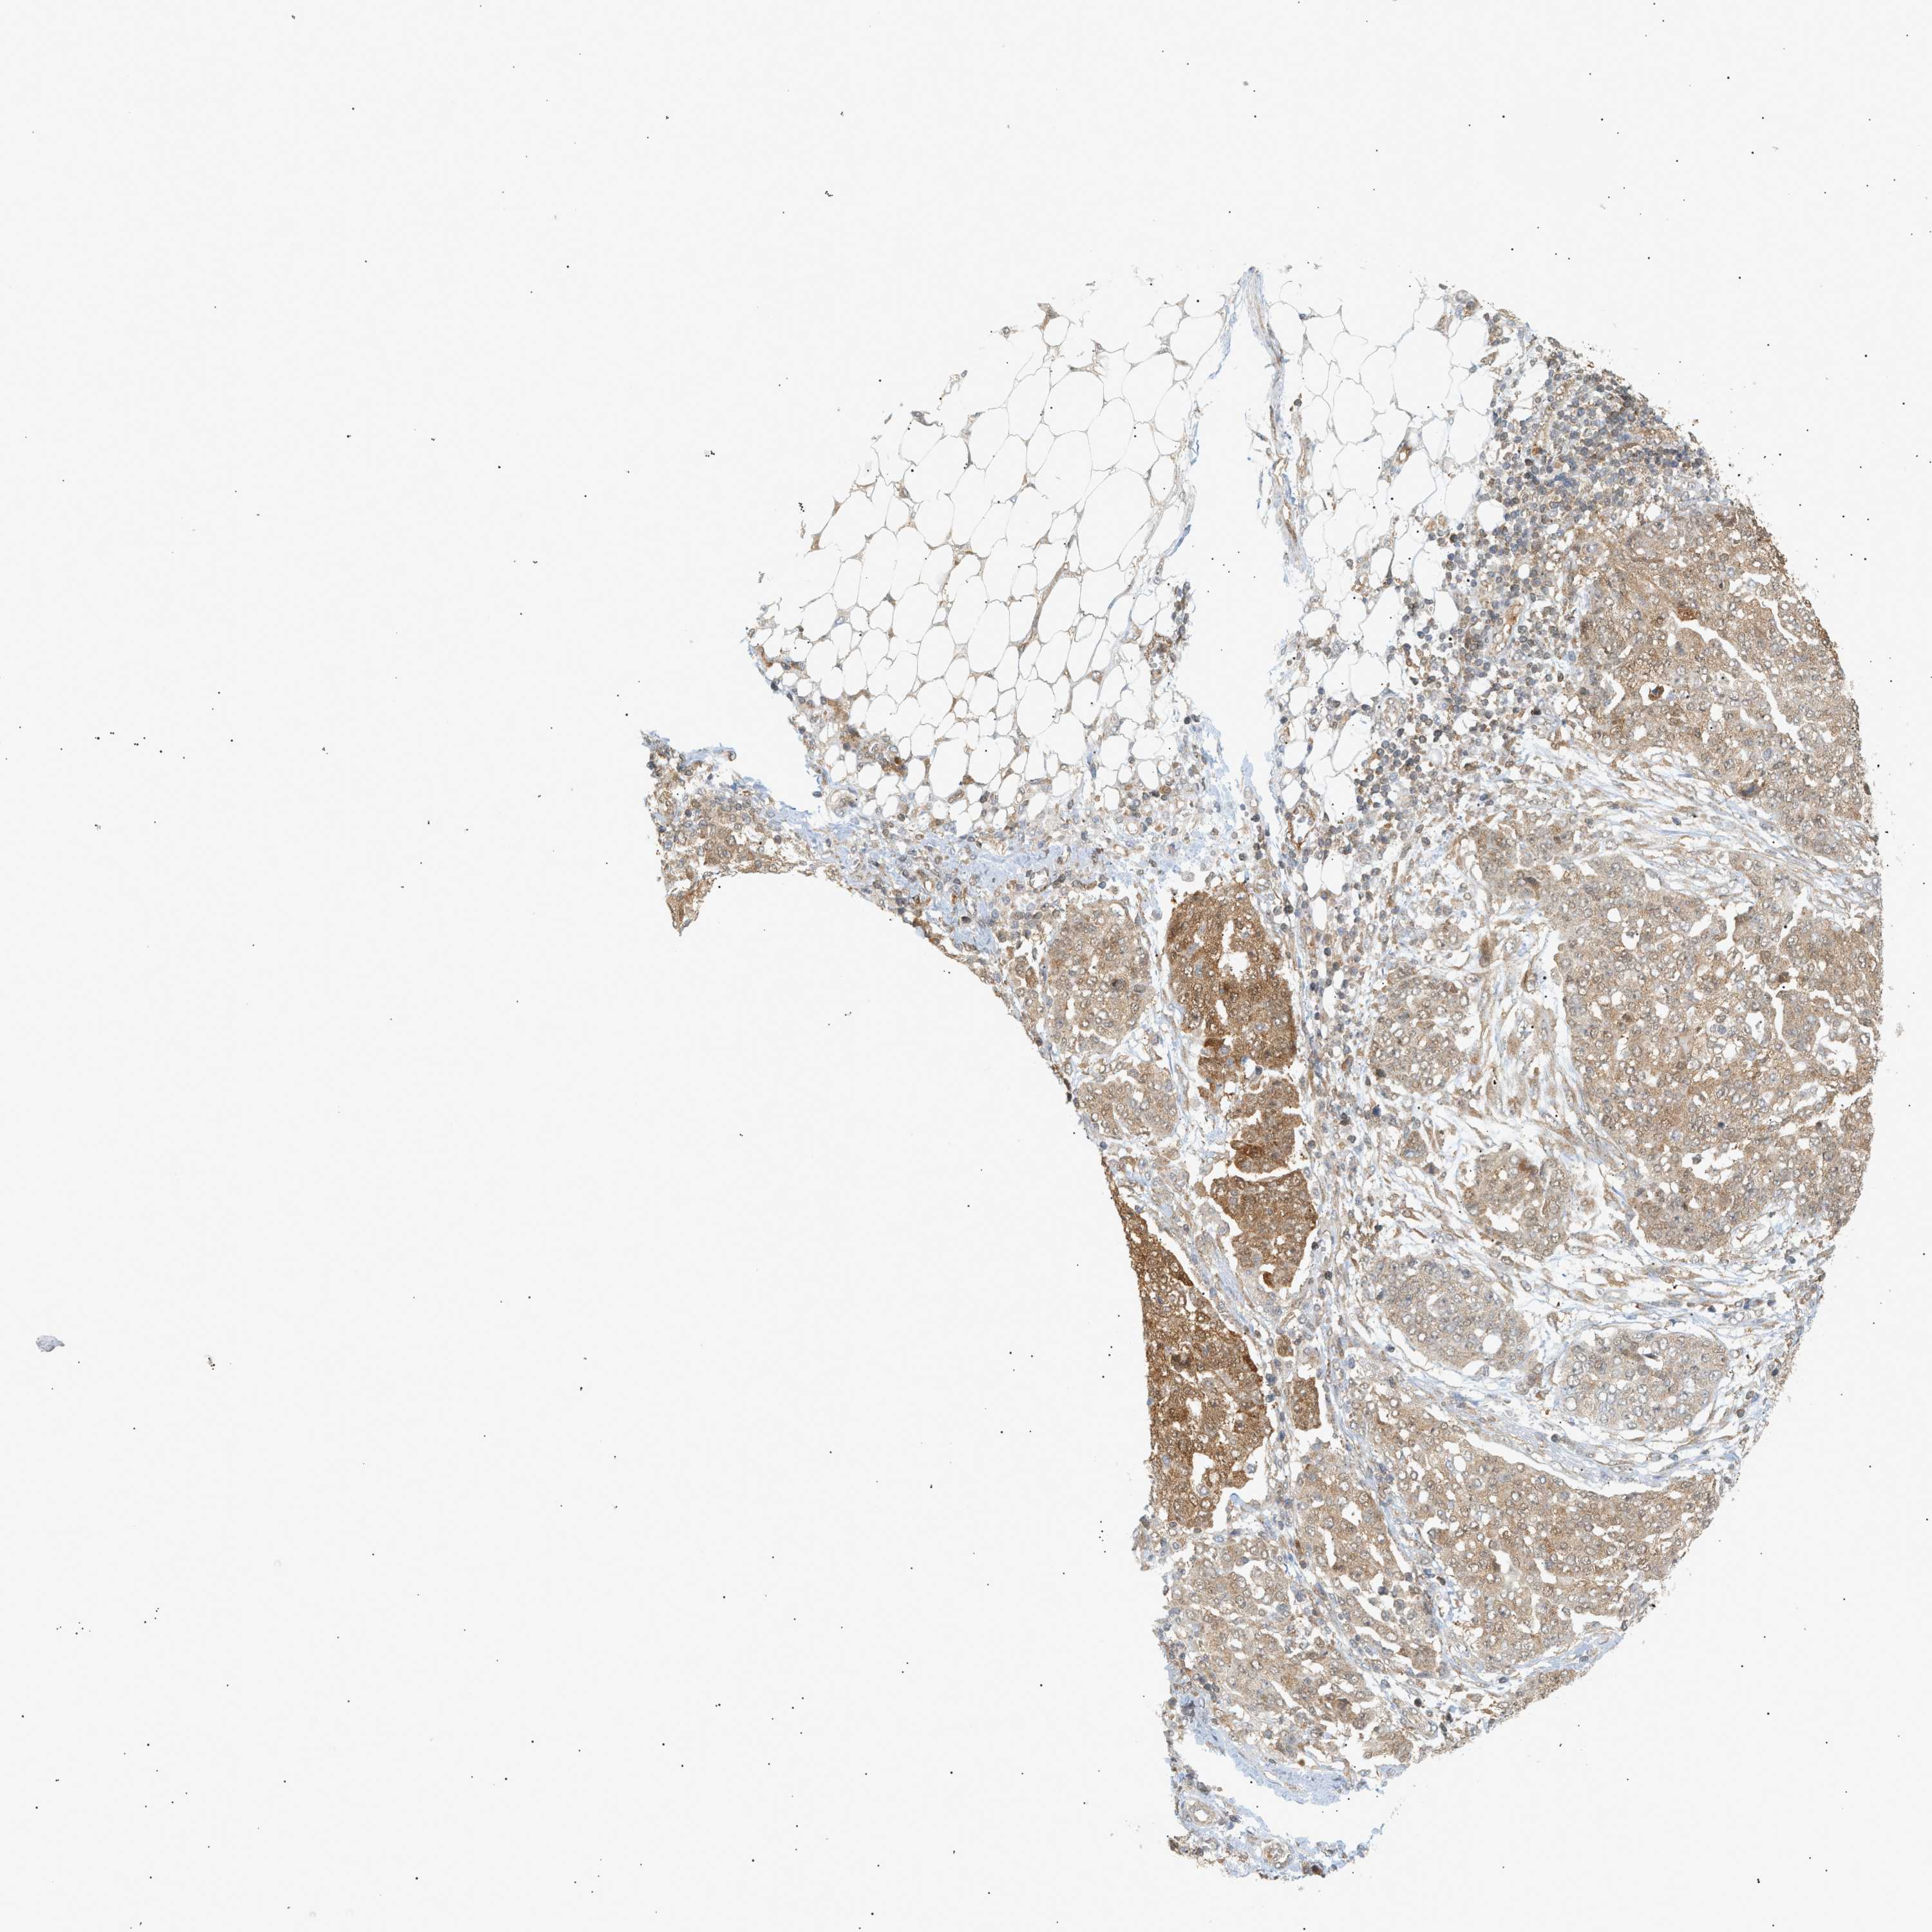

OVARIAN CANCER - Protein expressioni

A mouse-over function shows sample information and annotation data. Click on an image to view it in a full screen mode. Samples can be filtered based on level of antibody staining by selecting one or several of the following categories: high, medium, low and not detected. The assay and annotation is described here.

Note that samples used for immunohistochemistry by the Human Protein Atlas do not correspond to samples in the TCGA dataset.

Antibody stainingi

Antibody staining in the annotated cell types in the current human tissue is reported as not detected, low, medium, or high, based on conventional immunohistochemistry profiling in selected tissues. This score is based on the combination of the staining intensity and fraction of stained cells.

Each image is clickable and will lead to virtual microscopy that enables deeper exploration of all samples and also displays staining intensity scores, fraction scores and subcellular localization as well as patient and tissue information for each sample.

Antibody CAB005374

Cystadenocarcinoma, serous, NOS

Cystadenocarcinoma, mucinous, NOS

Carcinoma, endometroid

Carcinoma, NOS